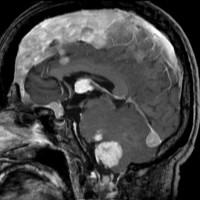

NF-2の多発性髄膜腫

赤の矢印が,両側の聴神経腫瘍です。黄色の矢印は, 多発性の髄膜腫です。蝶形骨縁髄膜腫,穹隆部髄膜腫,大脳鎌髄膜腫,大脳鎌テント接合部髄膜腫などいっぱいあります。これらは基本的に経過観察しますが,とても目立って大きくなるものがあれば摘出します。摘出には注意が必要で,近い将来また手術になるかもしれないので,次回の手術もできるように工夫して開頭手術しなければなりません。でないと,次の手術での合併症が増えます。また一回の開頭で近傍の硬膜や腫瘍を可能な限り摘出してしまうことも大切です。でないと,限りなく手術を繰り返すことになります。